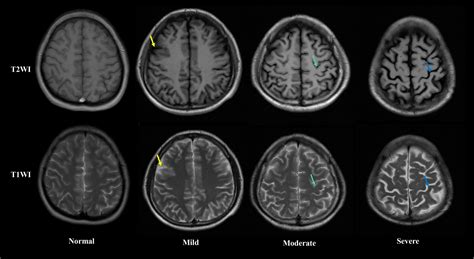

One of the key findings from the Kip Kinkel brain scan was the presence of reduced activity in the prefrontal cortex, a region of the brain crucial for executive functions such as impulse control and decision-making. This area is often referred to as the brain's "control center," and its dysfunction can lead to impulsive and aggressive behavior. Additionally, the scan showed abnormalities in the amygdala, a region involved in processing emotions, particularly fear and aggression.

These neurological abnormalities suggest that Kinkel may have had difficulty regulating his emotions and controlling his impulses, factors that could have contributed to his violent actions. However, it is important to note that neurological findings alone do not explain complex behaviors like school shootings. Environmental, psychological, and social factors also play significant roles.

For example, a comparative study might reveal that individuals with reduced prefrontal cortex activity are more likely to engage in impulsive violent acts, while those with amygdala abnormalities may exhibit heightened aggression and emotional dysregulation. Understanding these distinctions can guide the development of targeted therapies, such as cognitive-behavioral therapy or pharmacological interventions, to address specific neurological deficits.